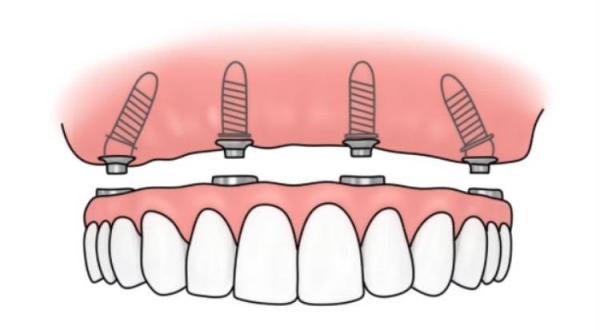

如果你缺了半口或全口牙,數(shù)字化種植的優(yōu)勢(shì)較大。傳統(tǒng)種牙需要種很多顆,手術(shù)時(shí)間長、創(chuàng)傷大。而數(shù)字化種植可以用更少的種植體支撐整排假牙,比如All-on-4技術(shù),只需要種4顆種植體就能支撐半口假牙。